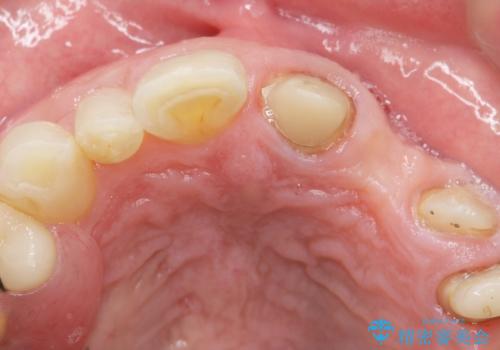

左上2欠損部の軟組織のボリュームが少なくポンティック部に食渣がたまりやすい歯肉形態であったため、歯槽堤増大術も提案しましたがご希望されませんでした。

ご希望により最終補綴前にホームホワイトニングを行っております。

最終補綴前に右上321の結合組織移植術(CTG)を希望されたため、大元院長に行って頂きました。

クラウンの種類:オールセラミッククラウン スタンダード